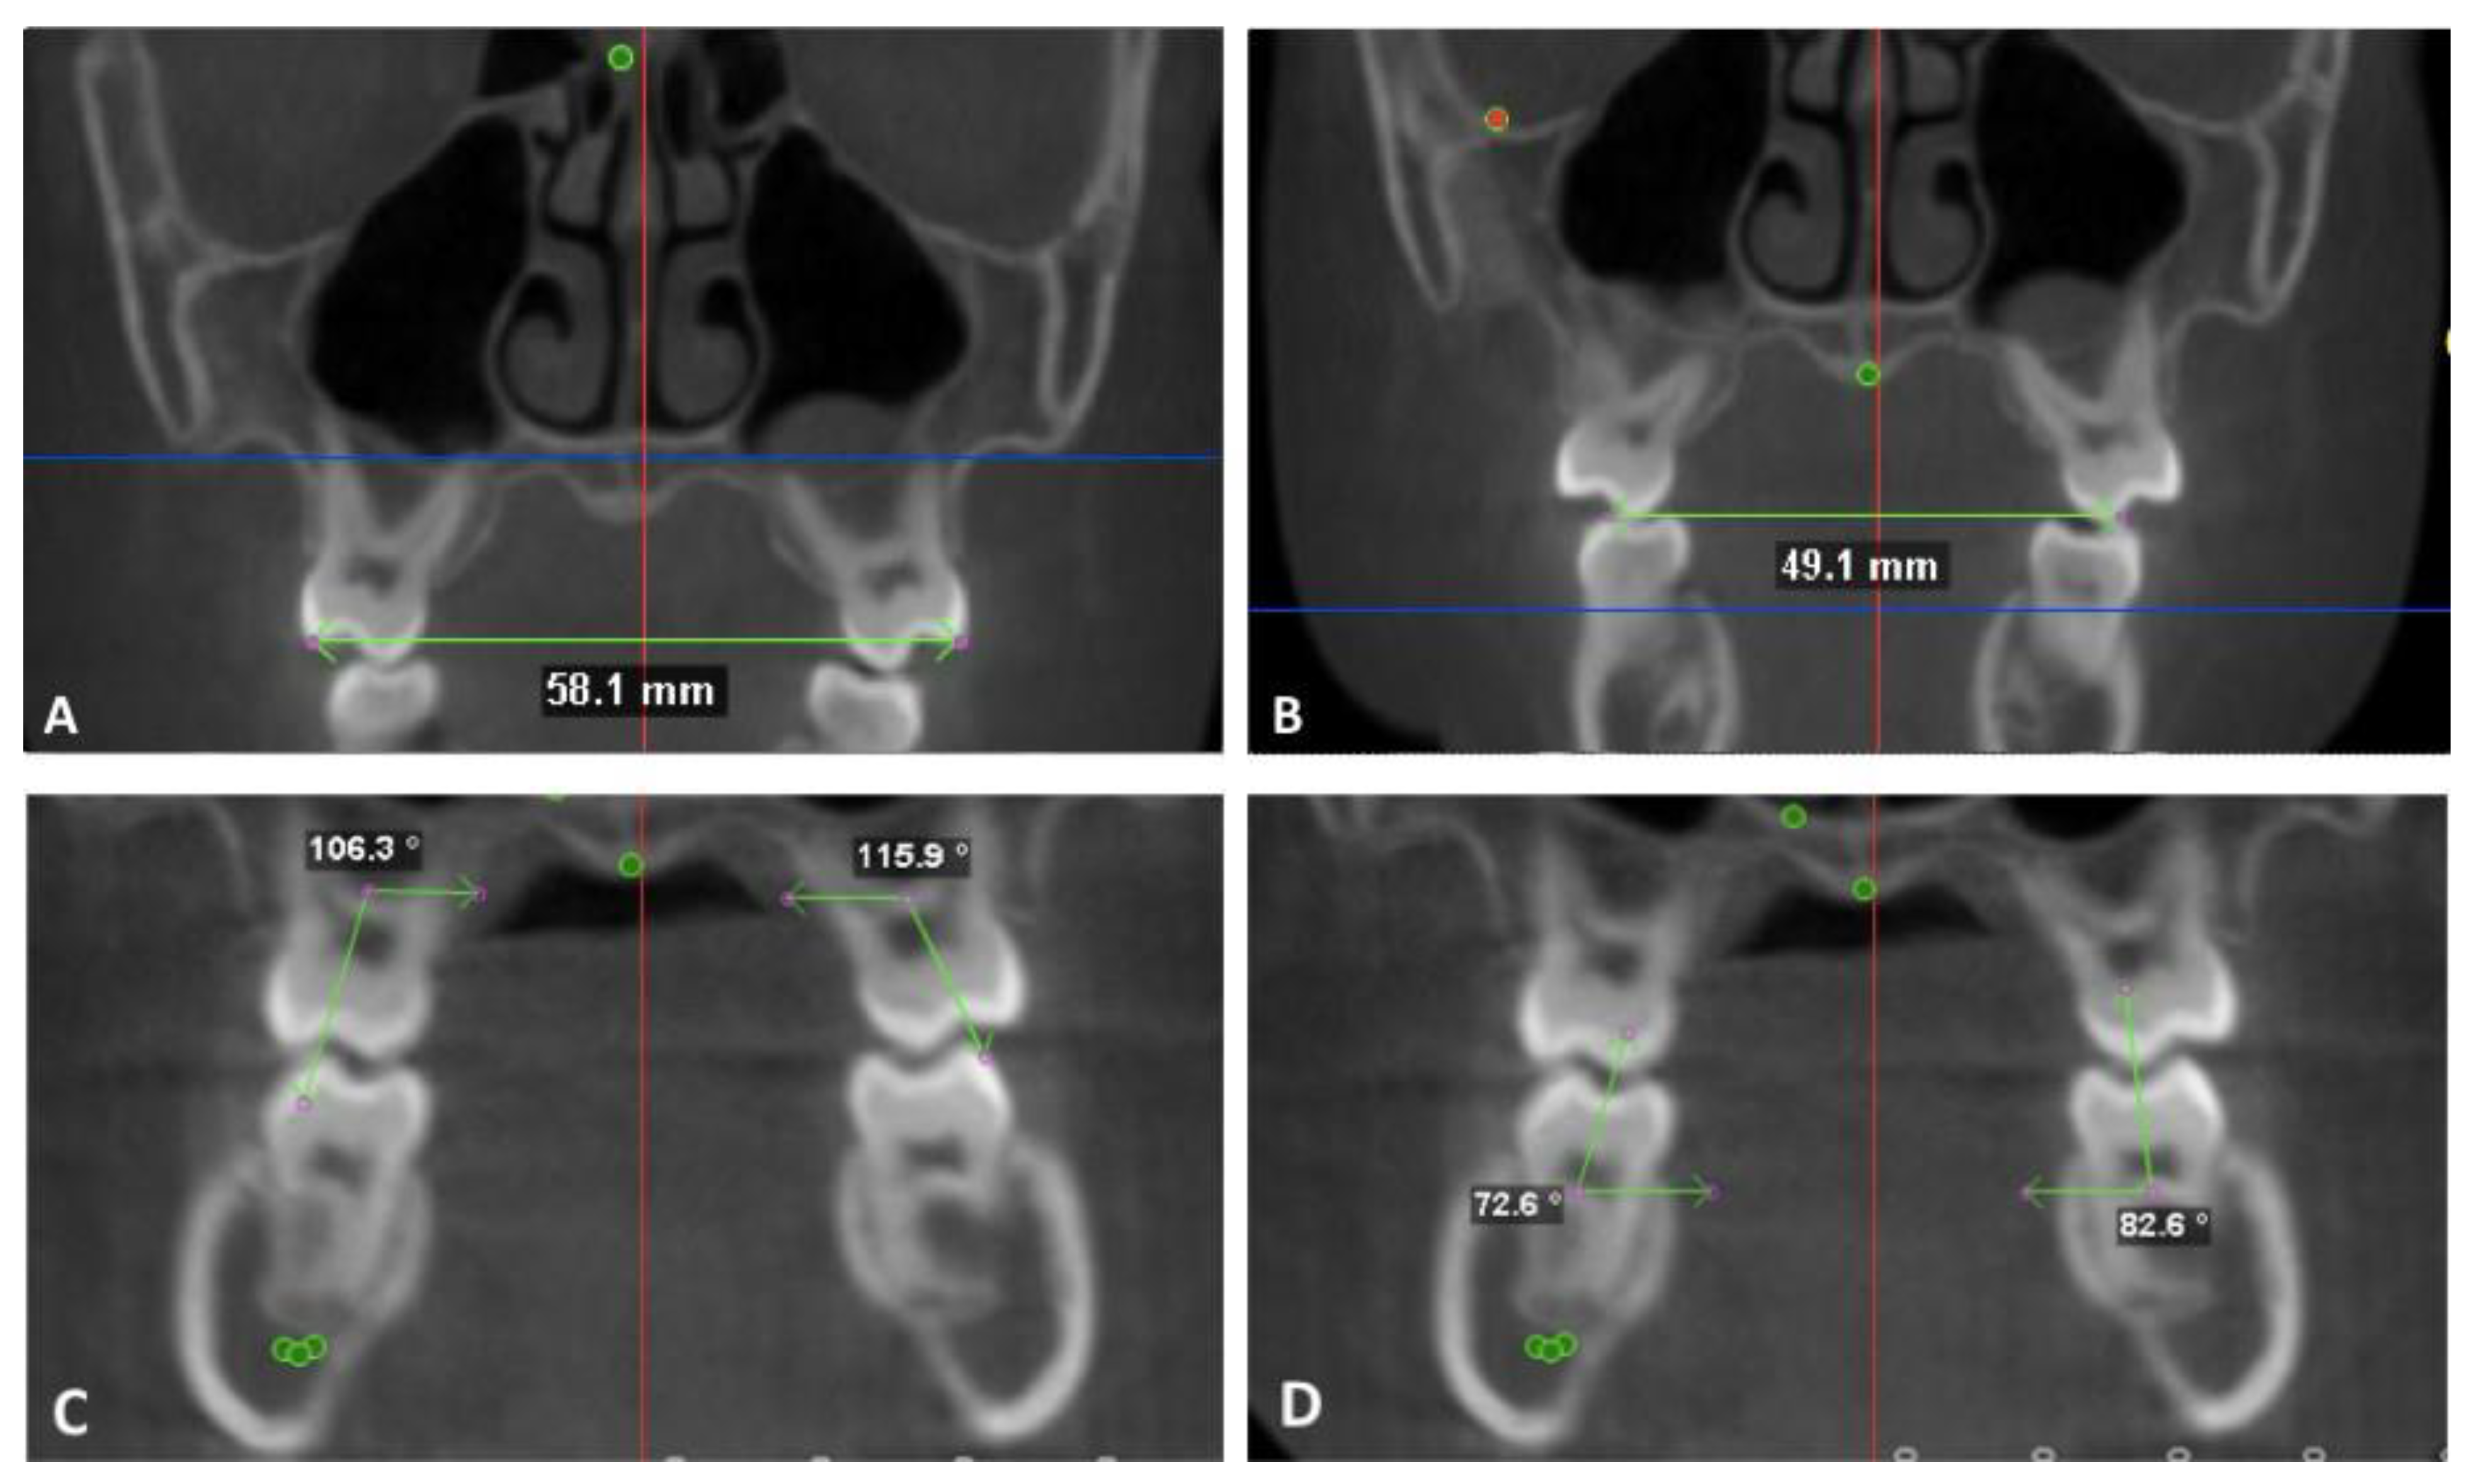

2.3. Skeletal Measurements

- Anterior nasal width: when viewed from the frontal, the distance between the most convex point along the lateral nasal margins.

- Io-Io: when viewed from the frontal, the distance between the mesiodistal and inferosuperior center of the infraorbital foramen.

- Mx-Mx: when viewed from the frontal, the distance between the most concave point in the infrazygomatic area.

- Ag-Ag: when viewed from the frontal, the distance between the most concave point in the lower mandibular border.

- Mf-Mf: when viewed from the frontal, the distance between the most mesial margin of the mental foramen.

- Go-Go: when viewed from the inferior, the distance between the mesiodistal center at the most infero-posterior point of the inferior mandibular border.

- Gonion triangle: when viewed from the inferior, the angle between the left and right gonion and menton. The points are identified on a profile view and the angle lies in the axial plane.

- U6 nasal width: the distance between the most convex point along the lateral nasal wall on a coronal section at the mesiodistal center of the maxillary 1st molar.

- Cd-Cd lateral: the distance between the most lateral points of the condyle that could be seen on axial cross sections of the condyle.

- Cd-Cd middle: the average of Cd-Cd medial and Cd-Cd lateral and represents the midpoint of the condylar head.

- Cd-Cd medial: the distance between the most medial points of the condyle that could be seen on axial cross sections of the condyle.